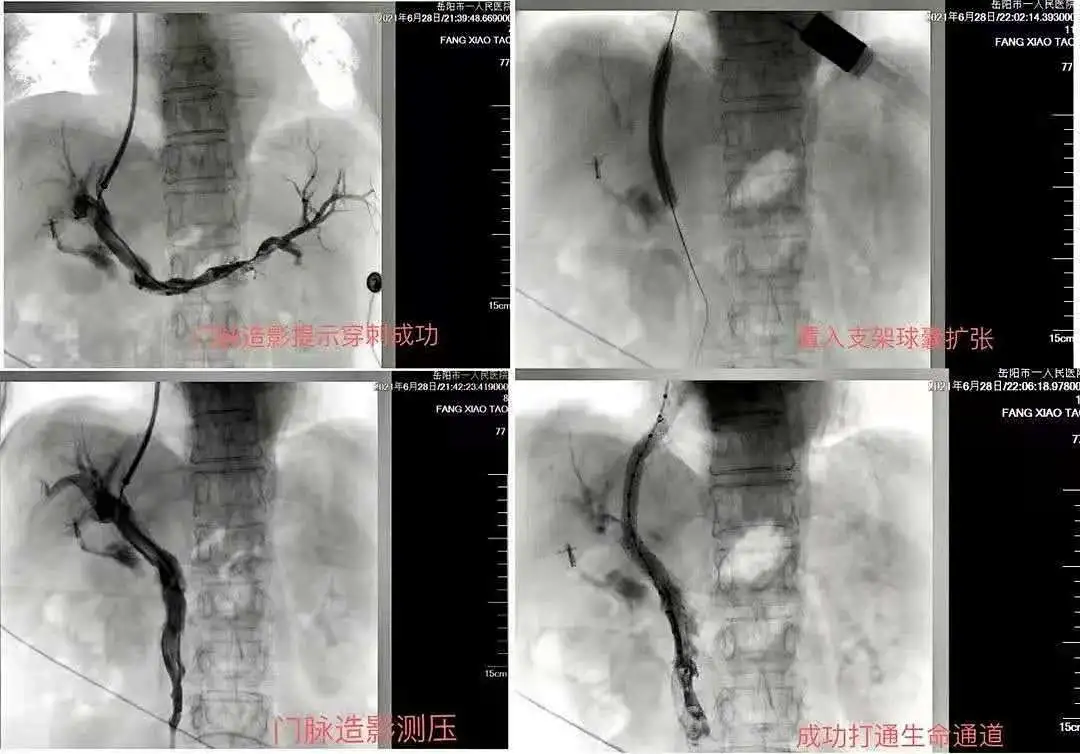

8月29日,内科消化中心成功完成第3例TIPS(经颈静脉肝内门体分流术)手术,为肝硬化门脉高压患者打通生命通道。